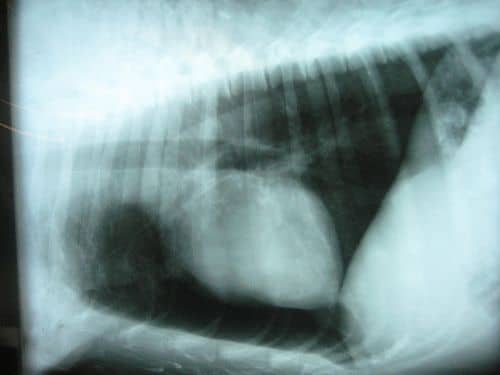

Rekeszsérv: Ebben az esetben a rekeszizom egy része nem fejlődik ki és az izom rostjai között keletkezett nyíláson az azonos oldali hasi szerve(ek) a mellüregbe türemkedik. Az is lehet, hogy csupán a gyomor egy része kerül a rekesz vonala fölé, mert a túl rövid nyelőcső oda felhúzza. A rekeszsérv baloldalt gyakoribb.A tünetek a sérvtartalom nagyságától függenek. Kisebb sérvre általában visszatérő gyomortáji fájdalom, hányás hívja fel a figyelmet. A nyelőcső becsípődés nyelési nehézséget és makacs hányást vált ki. Rendkívül nagyfokú sérv, féloldali rekeszizomhiány vagy a rekeszizom féloldali fejletlensége, tónustalansága esetén a mellüregbe nyomult gyomor és belek légzési és keringési zavarokat okozhatnak, és a beteg már újszülött korban életveszélybe kerül.A gyanút röntgen-, ultrahangvizsgálat tisztázza.Kezelése műtét, amit biztos diagnózis esetén többnyire már újszülött korban elvégeznek.